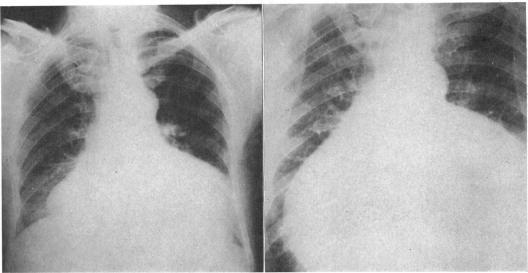

BEDFORD D E

Br Heart J. 1964 Jul;26(4):499-512. doi: 10.1136/hrt.26.4.499.